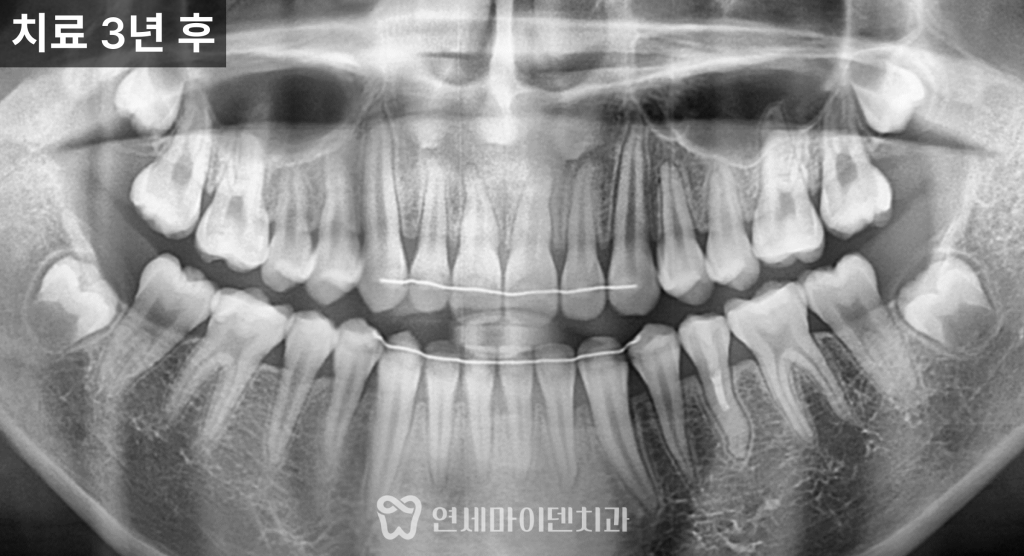

3년 경과, 치아의 변화

치료 후 가장 먼저 확인된 변화는

치아의 흔들림이 사라졌다는 점입니다.

이후 경과를 관찰한 결과

3년이 지나면서

뿌리 길이가 점차 늘어나고

두께도 함께 증가한 모습이 확인되었습니다.

이는 치근단 형성술을 통해

뿌리 성장이 정상적으로 진행되었다는 의미입니다.

결과적으로

발치 없이 자연치아를 유지하면서

장기적으로 사용할 수 있는 기반을

마련한 케이스입니다.